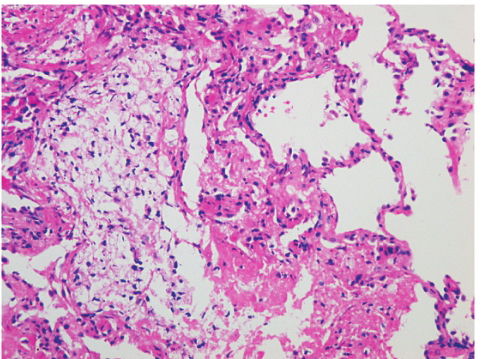

患者经伏立康唑治疗后双下肺实变影及渗出影明显吸收,但双肺下叶胸膜下可见磨玻璃影及间质增生,双侧胸膜不规则增厚。肺组织TBLB病理(2018-04-08,图3)显示(右下叶后基底段活检)肺泡壁慢性炎症细胞浸润,肺泡腔内见纤维素性渗出,肺泡上皮增生,结合临床,符合结缔组织病肺损伤。免疫组化结果:CK(+),VIM(+),CgA(-),Syn(-),TTF-1(0),WT-1(-),LCA(+),P63(-/+),NapsinA(+),P40(-/+)特殊染色结果:特染PAS(-),抗酸(-),银染(-)。至此,结合患者病史特点、影像学表现、病理结果和对伏立康唑、糖皮质激素以及免疫调节剂治疗反应良好,可做出最后诊断。

图3右肺下叶后基底段TBLB病理(HE,×400):见肺泡壁慢性炎症细胞浸润,肺泡腔内见纤维素性渗出,肺泡上皮增生